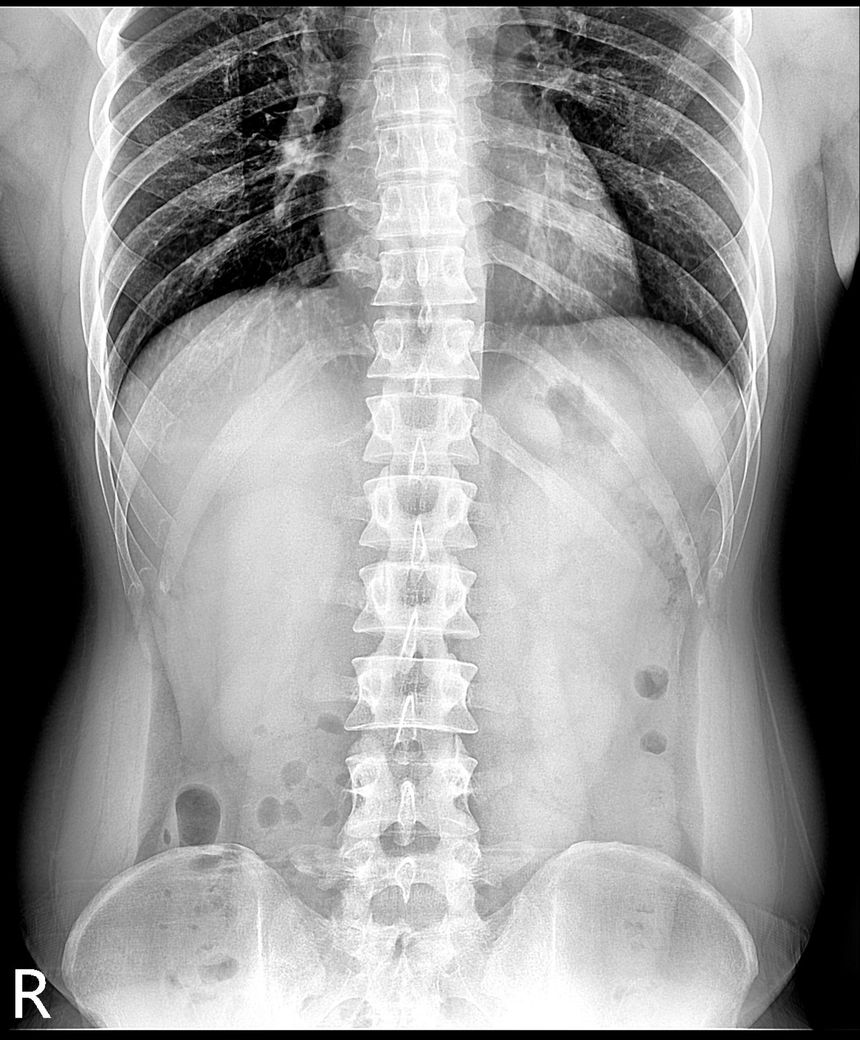

강직성척추염 의심(xray 및 mri 첨부)

인터넷 검색 후 강직성척추염을 알게 되어 말씀 드렸더니 스트레칭??을 해보시고 아닌 것 같은데 걱정이 된다고 하니 x-ray 및 mri를 찍어보자고 하셨습니다. (유전자검사는 채혈 후 대기 중)

xray 및 mri상에도 의심소견이 없다고 하셨는데

사진으로 염증이 있는지 확인 부탁드립니다.

강직성척추염과같은 염증성질환의경우 엑스레이로만은 확인하기가 어려운데요 다른 인자검사라던가 정확한 진단을위한 MRI검사등이 필요할수있습니다

올려주신 엑스레이나 MRI를 참고할 때, 또는 진료시 스트레칭을 통한 허리 및 천장관절의 유연선 평가와 개인에 따라 다르지만 대표적인 강직성 척추염의 증상이 크게 없는 것으로 보아 발생 가능성이 낮을 수 있습니다.

강직성 척추염은 주로 허리의 움직임 제한 및 영상검사에서 관절염에 해당하는 소견과, 혈액검사등에서 염증수치가 증가되어있는 경우가 많지만 이에 해당하지 않는다면 가능성은 낮다고 볼 수 있습니다.